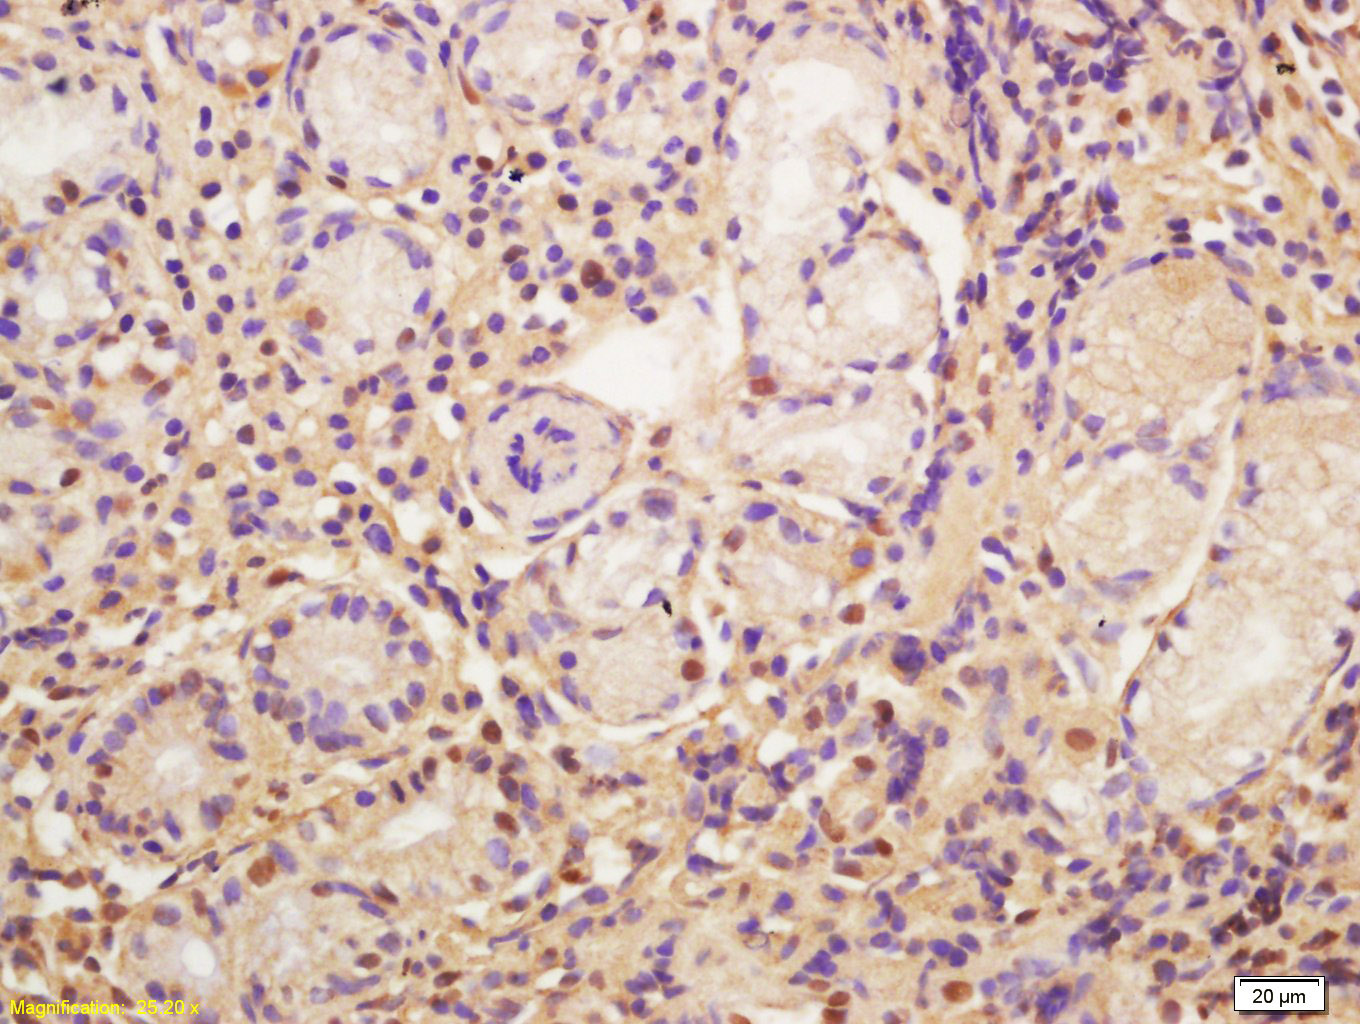

Tissue/cell: human gastric carcinoma; 4% Paraformaldehyde-fixed and paraffin-embedded; Antigen retrieval: citrate buffer ( 0.01M, pH 6.0 ), Boiling bathing for 15min; Block endogenous peroxidase by 3% Hydrogen peroxide for 30min; Blocking buffer (normal goat serum,C-0005) at 37∩ for 20 min; Incubation: Anti-CDC5L Polyclonal Antibody, Unconjugated(bs-15497R) 1:200, overnight at 4∑C, followed by conjugation to the secondary antibody(SP-0023) and DAB(C-0010) staining